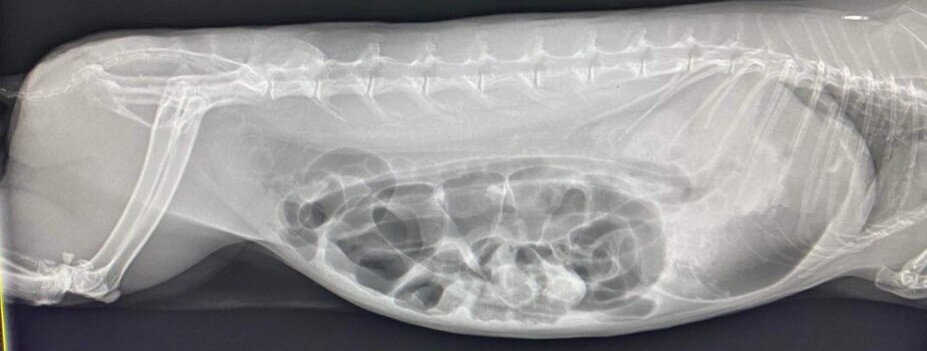

Your vet may recommend further diagnostic tests such as blood and urine testing, x-rays, CT (computed tomography) scanning, or an ultrasound to ensure that there is no potential cause that is missed.

Symptoms of gut stasis closely mimic the symptoms of a small intestinal obstruction. 99% of small intestinal obstructions in rabbits are trichobezoars, or hairballs, and these are more common when rabbits in particular, are moulting heavily. A dehydrated rabbit or guinea pig may also develop a small intestinal obstruction due to dehydration and the hardening of the gut contents.